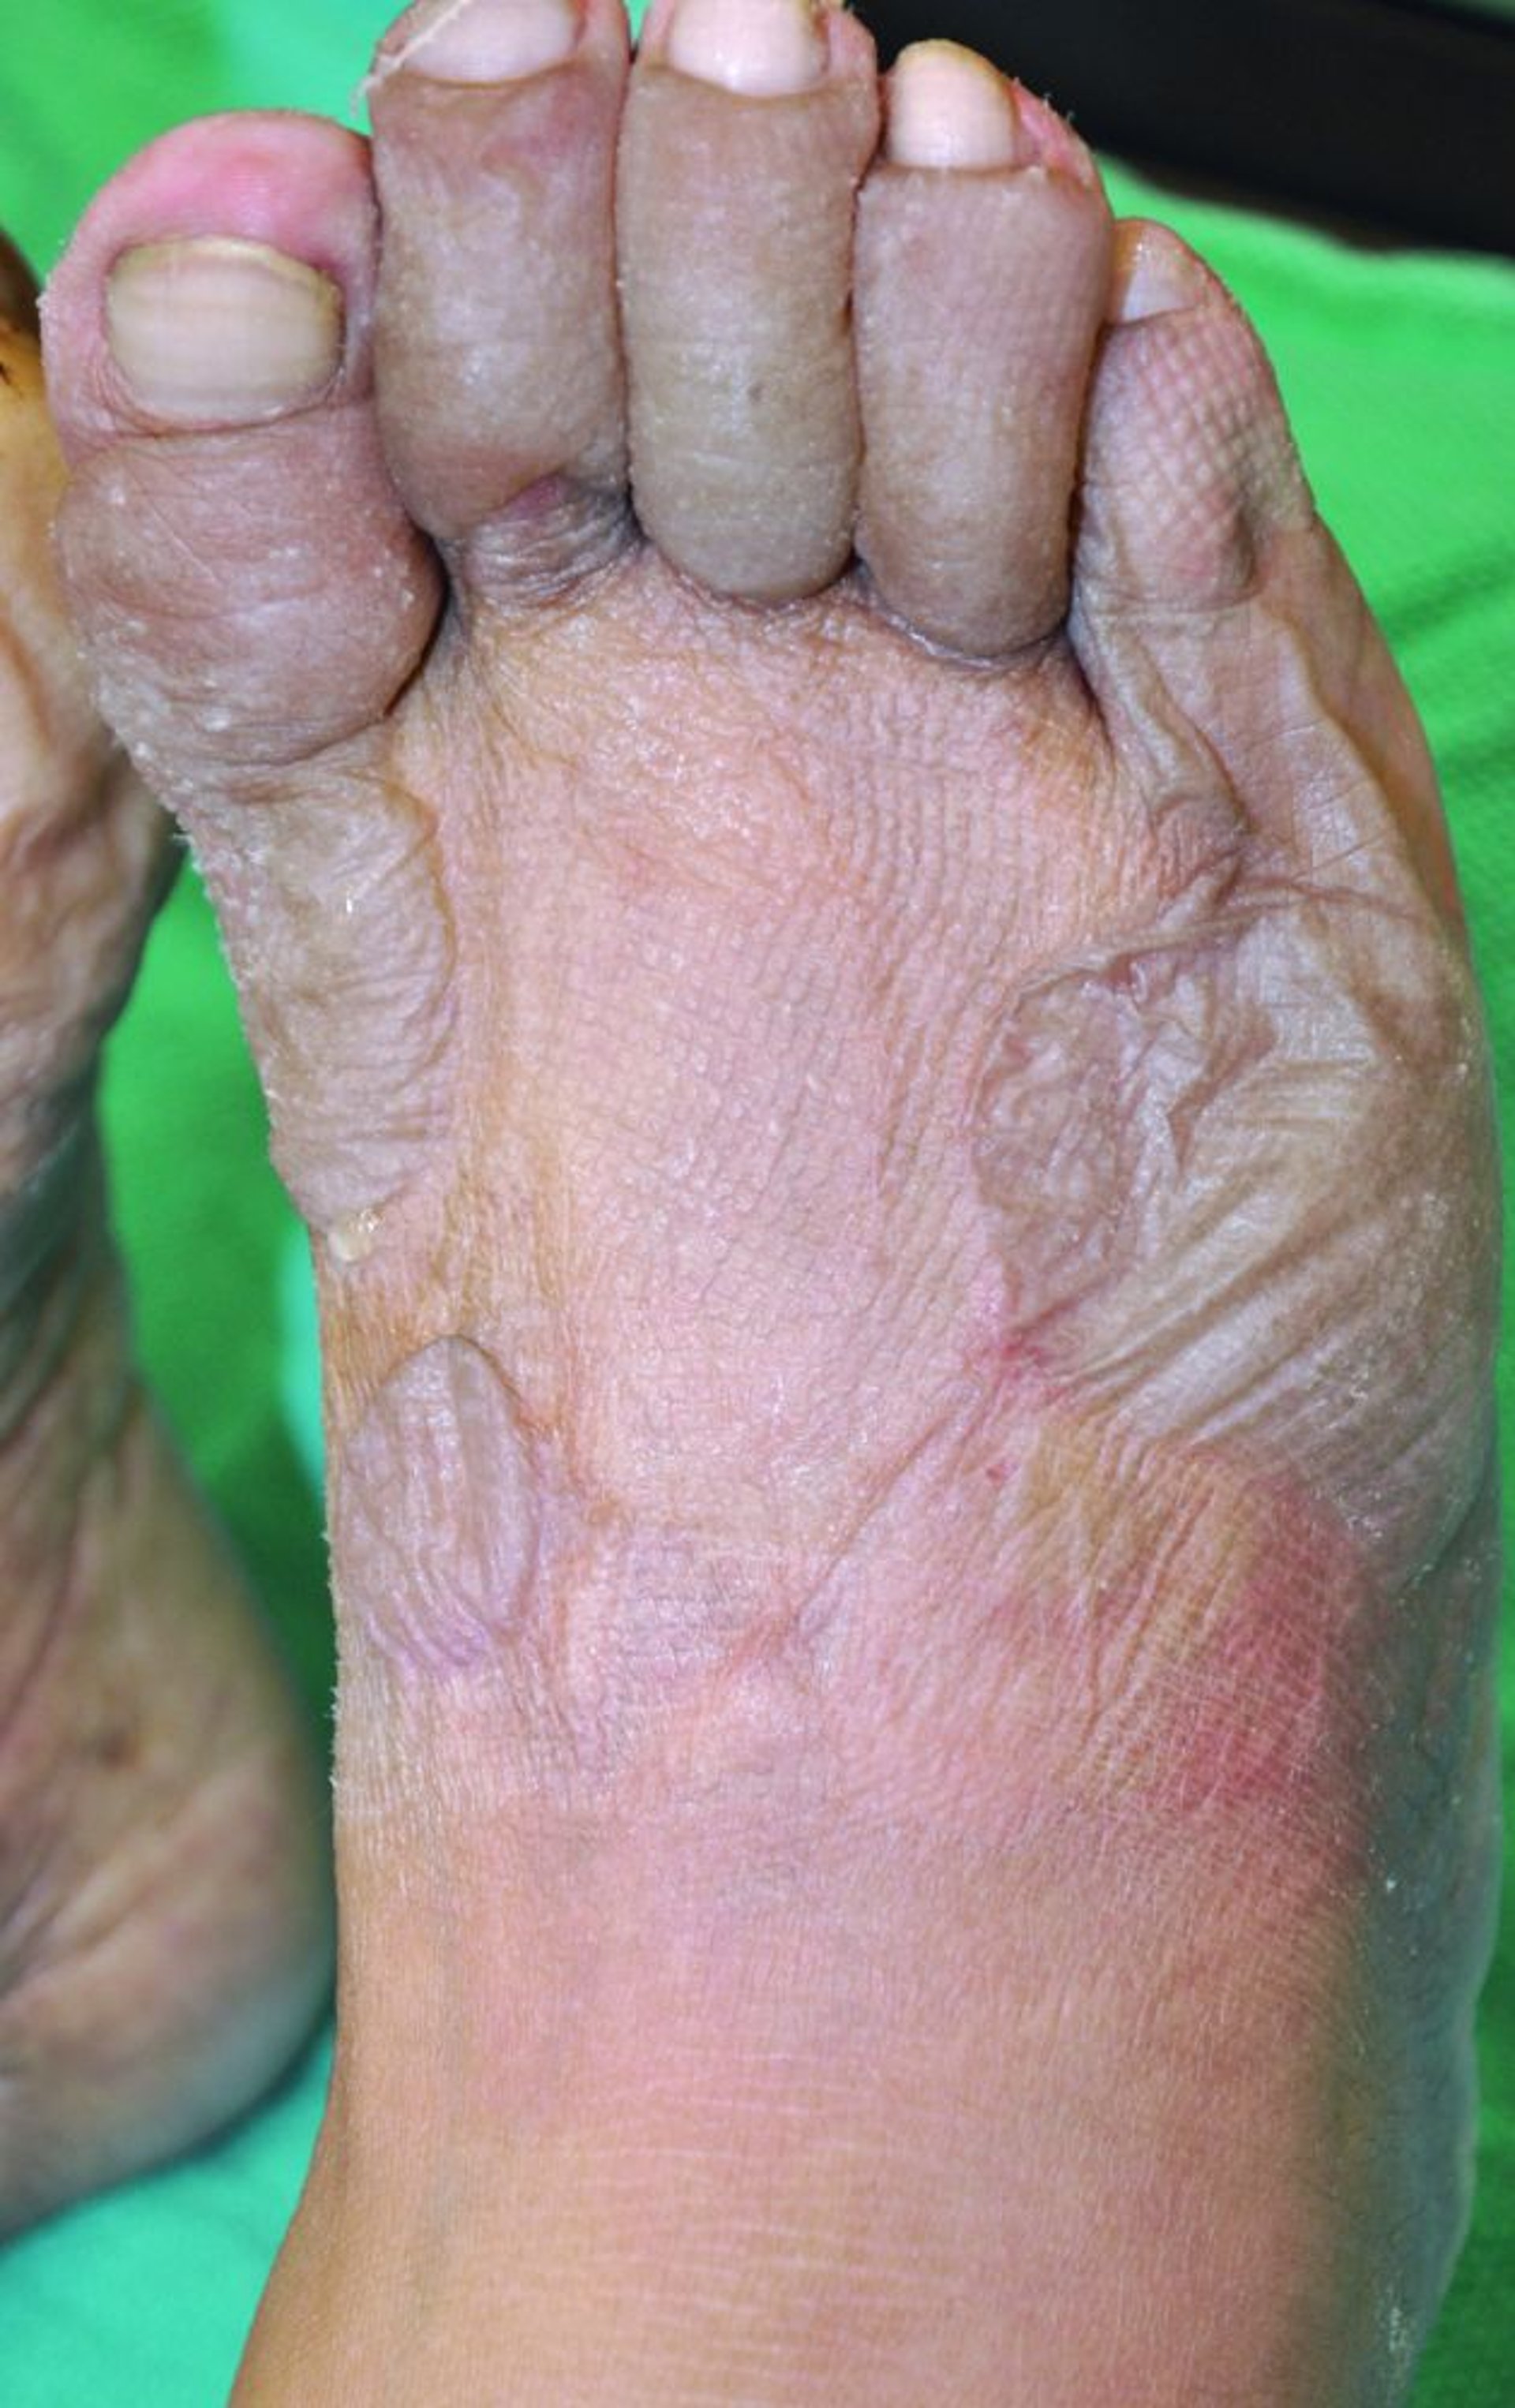

Geladura dos pés

Esta foto mostra leitos ungueais pálidos, pododáctilos acinzentados e edematosos, e bolhas no pé. A ausência de sangue nas bolhas sugere que a geladura é superficial e que é improvável a perda de tecido residual após a cicatrização.